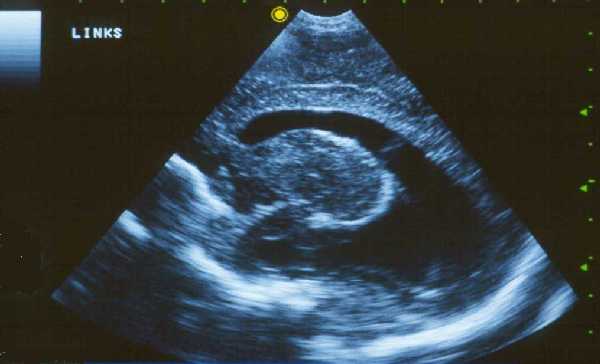

(3) 眼病,较先天性弓形虫病少见,有些不先天性感染但到成年后发作所致。

Photograph of fundus. Showing a heavily pigmented central choroidal lesion in a young person due to acquired toxoplasmosis. The whitish patches inside the lesion are areas where the sclera is exposed due to the necrosis of the retina. A sharply demarcated lesion, as seen in this photograph, is typical of both acquired and congenital toxoplasmosis. However, in some cases a more diffused lesion may be observed.